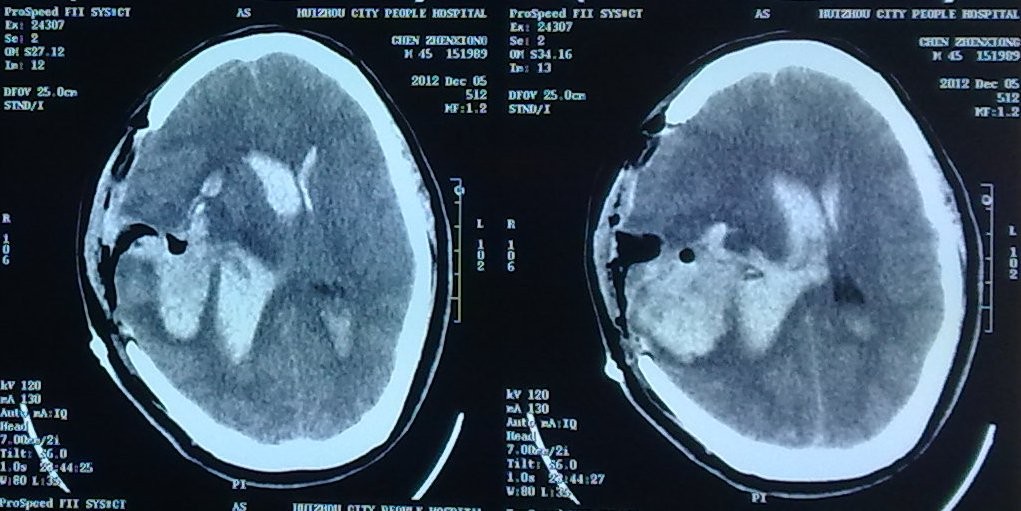

这是一位44岁的男性患者,因突发不省人事1小时急诊入院,初步诊断可能是右颞顶脑内血肿并脑疝、右颞顶动静脉畸形。因为脑疝形成需要急诊手术,术前无法作进一步检查来明确出血的原因,为了安全,第一次只作血肿大部分清除术,使脑疝缓解,瞳孔回缩,并不冒险深入探查。但是术后不久瞳孔又再次散大,复查头颅CT提示再出血,出血量超过第一次,约100多毫升,广泛占据大半个脑组织,形成巨大脑内血肿并脑室铸型血肿,深昏迷,濒死状态,若在以往该患者必死无疑。

1、巨大脑内血肿并脑室铸血肿